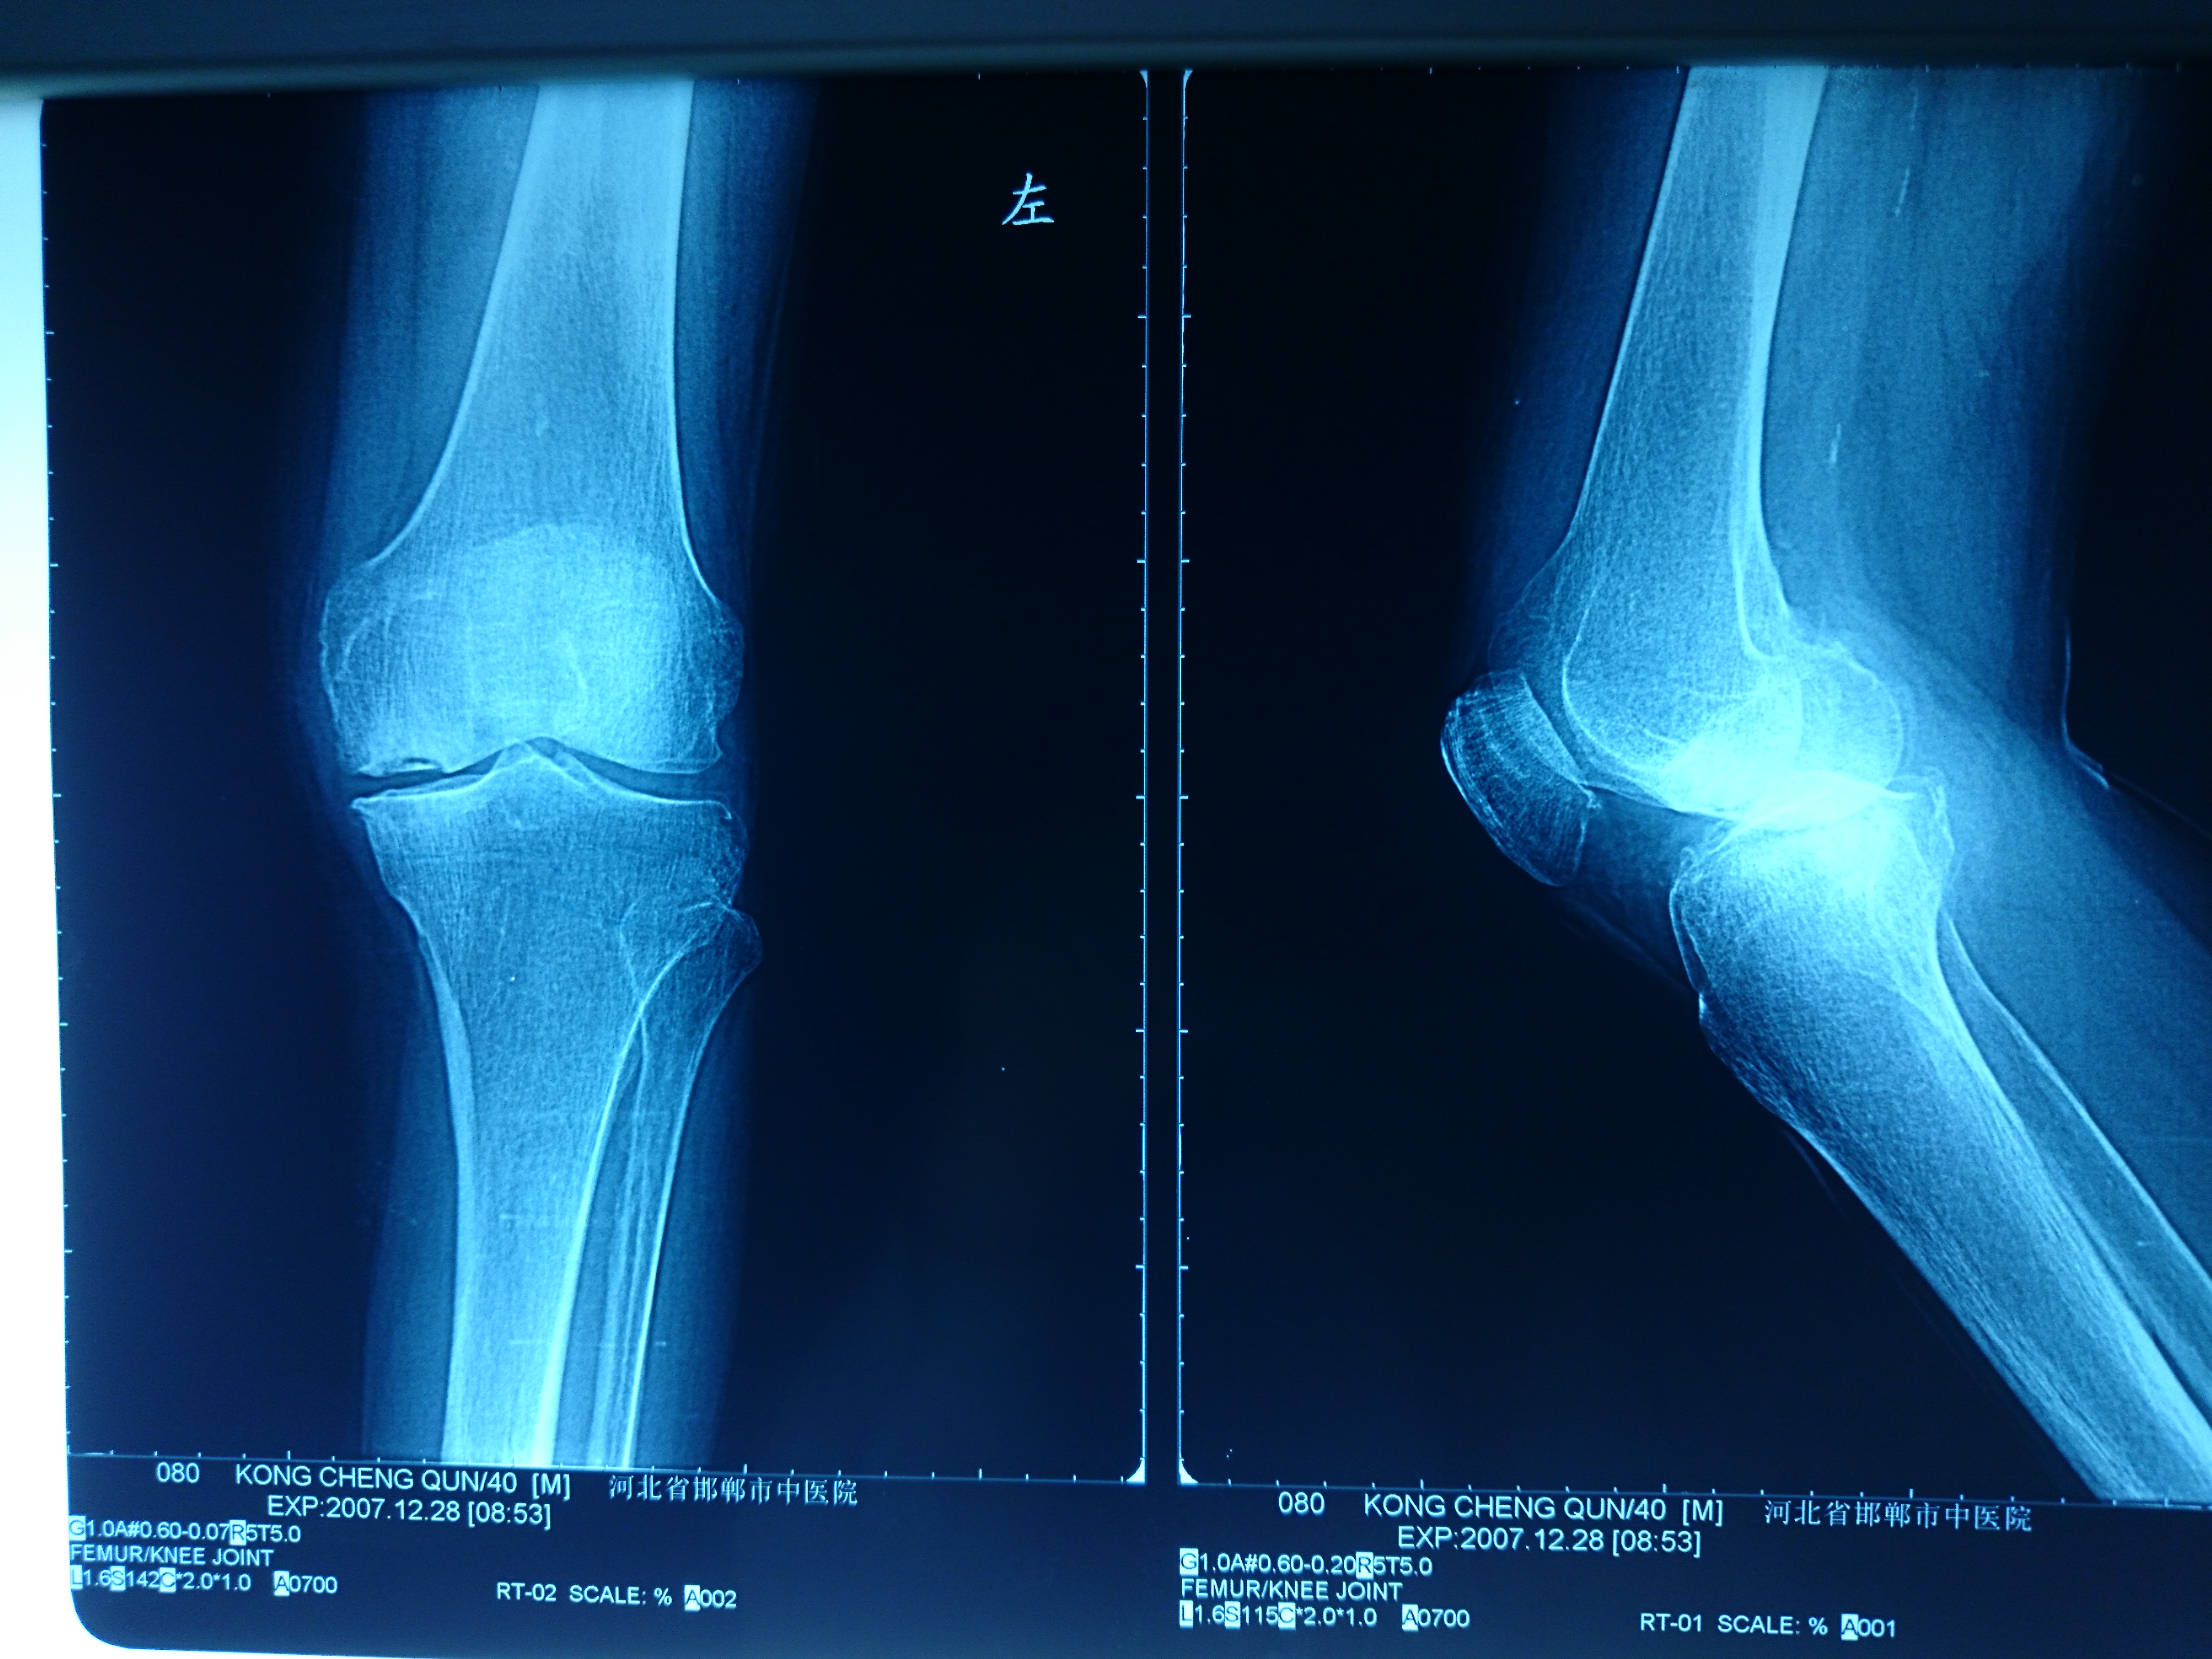

首页 > 张恒云工作室 > 影像资料 二十四